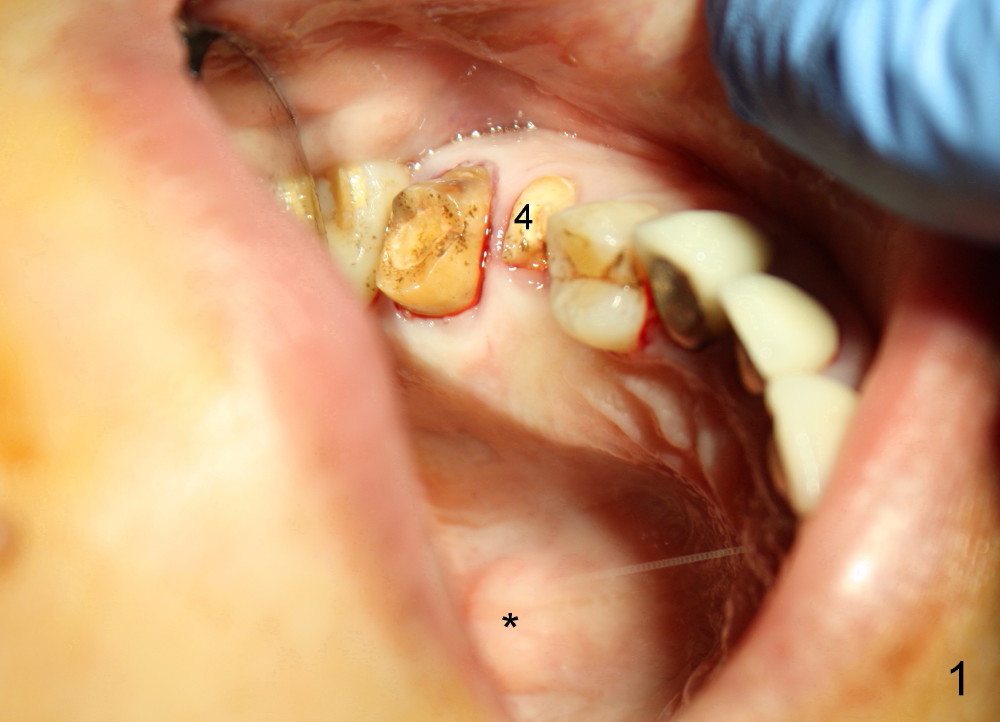

Mrs. Zhao, in her late forties, is apprehensive of dentistry. She has postponed implant placement for #4 for two months (Fig.1,2). Immediate implant is planned. Immediate provisional is provided if insertion torque is more than 45 Ncm. There are two conditions which are unfavorable to immediate provisional. First, she is probably a bruxer, as indicated by torus palatinus (Fig.1 *). Second, she bit off two crowns (joined) for #3 and 4 together.

When the tooth #4 is extracted, the apical socket is found to be large with granulation tissue, which is consistent with large periapical radiolucency (Fig.2 arrowheads). The depth of the socket is 17 mm, measured from the gingival margin. The mesiodistal and buccolingual dimensions of the root are 4 and 7 mm, respectively. A tissue-level tapered implant as wide and as long as possible, 4.5x20 mm, is to be placed (Fig.3 (tap drill), 4). The insertion torque is between 35 and 40 Ncm.